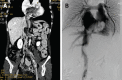

Intravenous leiomyomatosis (IVL), showing unusual growth patterns of uterine leiomyoma, is a rare neoplasm characterized by intravascular proliferation of a histologically benign-looking smooth muscle cell tumor mass, but not invading the tissue. To date, less than 300 cases have been reported and fewer than 100 cases with cardiac involvement. Imaging characteristics of IVL are still not clear so it is usually misdiagnosed before surgery. A 36-year-old woman, who had undergone hysterectomy due to hysteromyoma, presented with shortness of breath after activities. Imaging showed IVL with mass involvement of the left ovarian vein, left renal vein, left external and common iliac vein, as well as within the inferior vena cava (IVC), extending into the right atrium. The operation demonstrated that the mass had no stalk and had well-demarcated borders with the wall of the right atrium and IVC. The patient underwent a one-stage combined multidisciplinary thoraco-abdominal operation under general anesthetic. Subsequently, the pathology report confirmed IVL. IVL should be considered in a female patient presenting with an extensive mass in the right side of the heart. Imaging technology, such as echocardiogram, contrast-enhanced computed tomography and magnetic resonance imaging, can provide important information to reveal the mass, the range and path of the lesion, and relates to the surgical plan decision. Consequently, perfect and exact image examination is very necessary pre-operation.